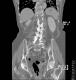

CT colon 38

Datortomografi av tjocktarmen (colon) med infunderad luft i tarmen samt med kontrast i blodbanan. Koronar bildserie.

CT multislice 16